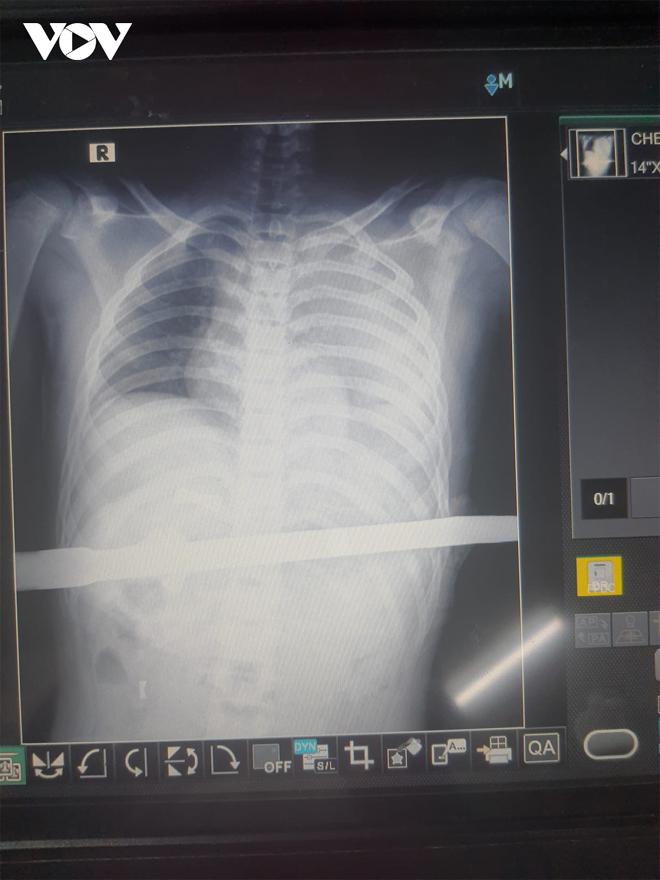

Kết quả siêu âm, bệnh nhân có tràn máu ổ bụng và màng phổi với dị vật xuyên thấu bụng ngực. Bệnh nhân được bác sĩ hồi sức tích cực, truyền máu và tiến hành phẫu thuật. Quá trình phẫu thuật, các bác sĩ phát hiện lưỡi dao xuyên thủng gan trái, dạ dày và cơ hoành. Hơn 2 giờ thực hiện ca phẫu thuật, bệnh nhân qua cơn nguy kịch và tiếp tục được các bác sĩ theo dõi hồi sức.